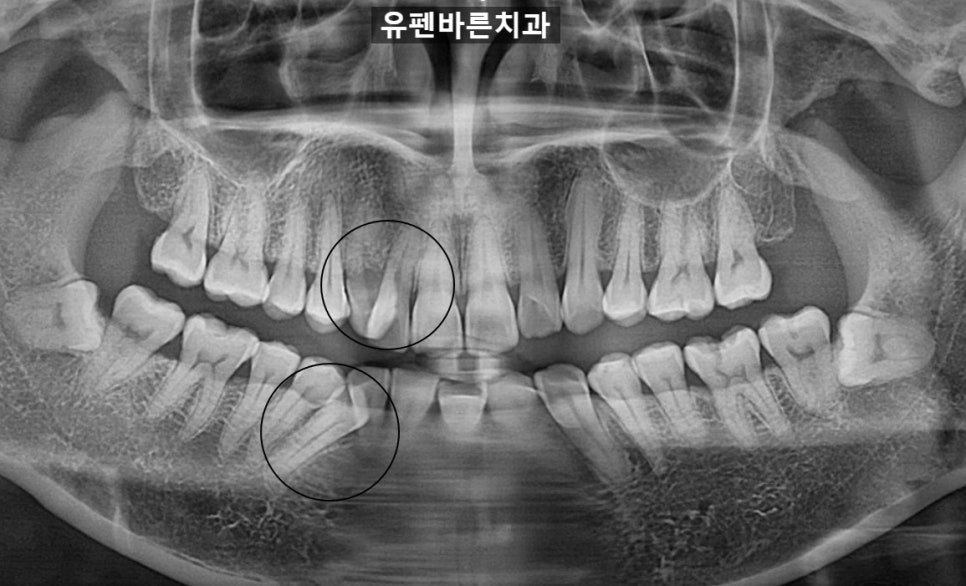

엑스레이를 찍어보니

사진과같이

치아들이 겹쳐 보이는걸

확인하실 수 있습니다.

'삐뚤빼뚤한 치아와 덧니'가

고민이셧던 환자분의

치아 상태는

공간 확보를 위해

발치가 필요한 상황 이었답니다

환자분의 동의를 구하고

오른쪽 위, 아래

각 4번째 치아를

발치했습니다.